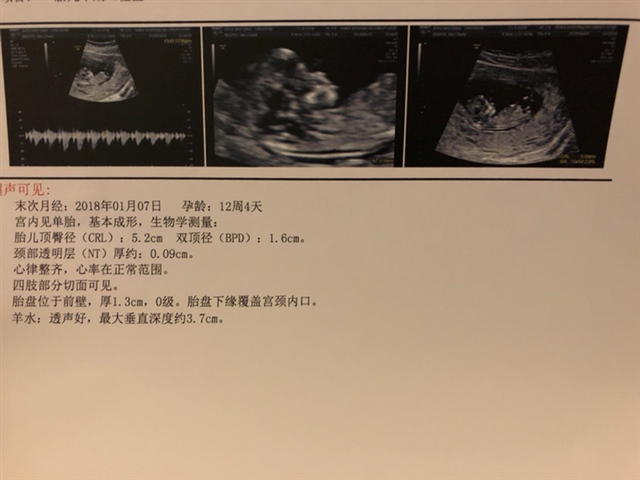

没说胎盘低置?

绿豆娃娃2GjP[帖主]:说了,让我注意一下,后期大点了应该会上去